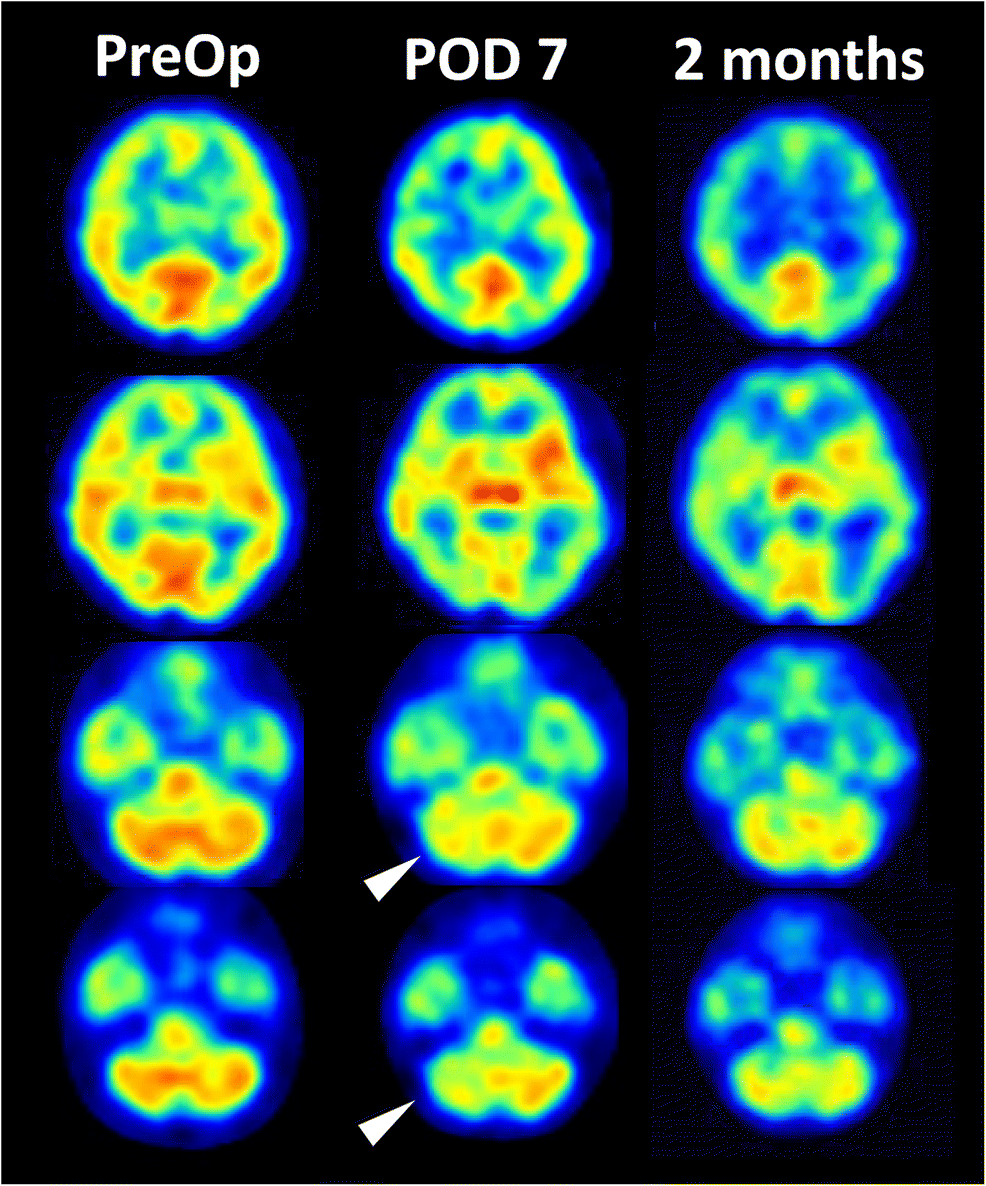

Figure 1 Crossed Cerebellar Diaschisis As An Indicator Of Severe Cerebral Hyperperfusion After Direct Bypass For Moyamoya Disease Springerlink

Crossed Cerebellar Diaschisis Radiology Case Radiopaedia Org

Crossed Cerebellar Diaschisis Radiology Reference Article Radiopaedia Org

Crossed Cerebellar Diaschisis Springerlink

Pet Imaging Of Crossed Cerebellar Diaschisis After Long Term Cerebral Ischemia In Rats